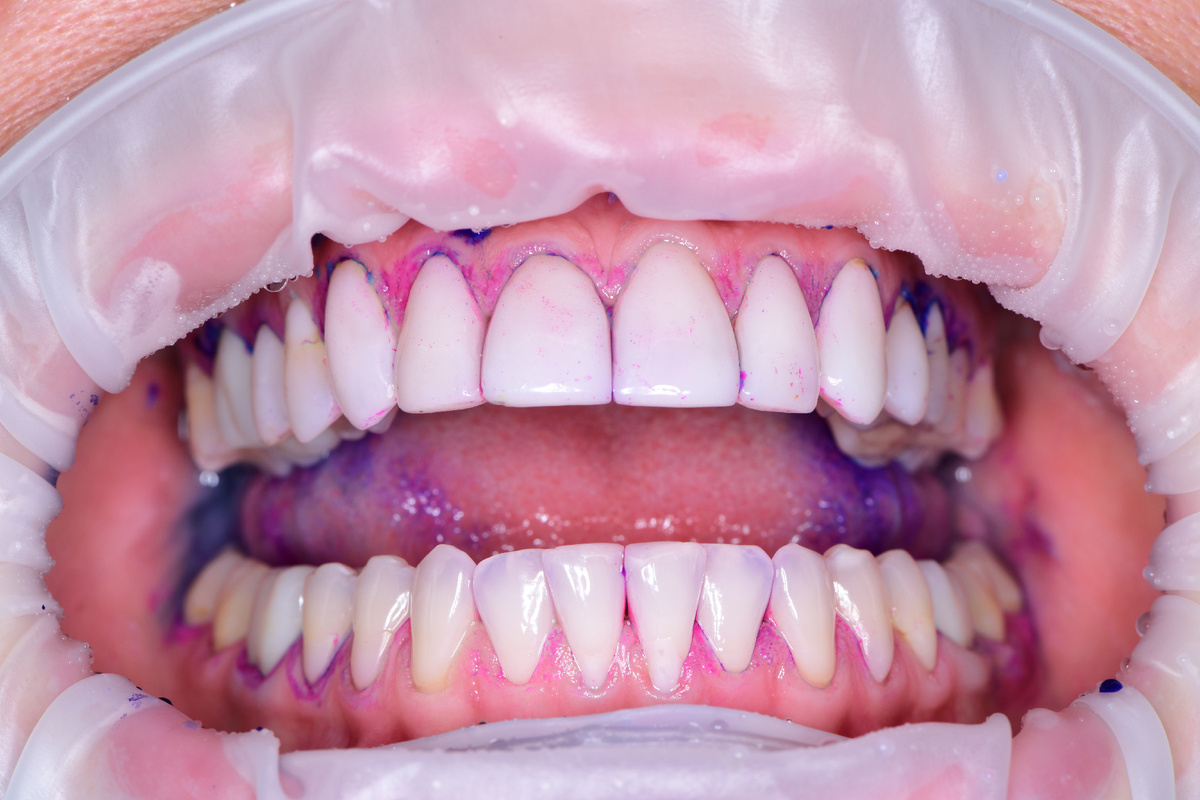

Передние верхние зубы отреставрированы композитом от клыка до клыка

В случае Елены на передних зубах с реставрациями практически нет налёта. Соответственно мелкоабразивный порошок AirFlow с добавлением эритритола прекрасно справится с очищением и заодно заполирует композит для того, чтобы бонусом к хорошей гигиене вернулся и блестящий оттенок передним композитным реставрациям.

Со временем реставрации начинают тускнеть и уже не так блестят как в первый день. На фото выше 👆 наглядно видно то, что реставрации на верхней челюсти имеют блеск только ближе к режущему краю, а собственные зубы на нижней челюсти (где нет композита) блестят очень ярко

Особенность реставраций из керамики заключается в том, что у них гладкая поверхность, блеск которой сохраняется много-много лет при регулярной гигиене. Керамика в этом смысле "благодарный" материал, в отличие от "пористых" композитных реставраций. "Пористость" композита видна при окрашивании индикатором, выглядят как мелкие точки, это отчётливо видно на фотографии ниже 👇

При окрашивании видны "поры" на композитных реставрациях